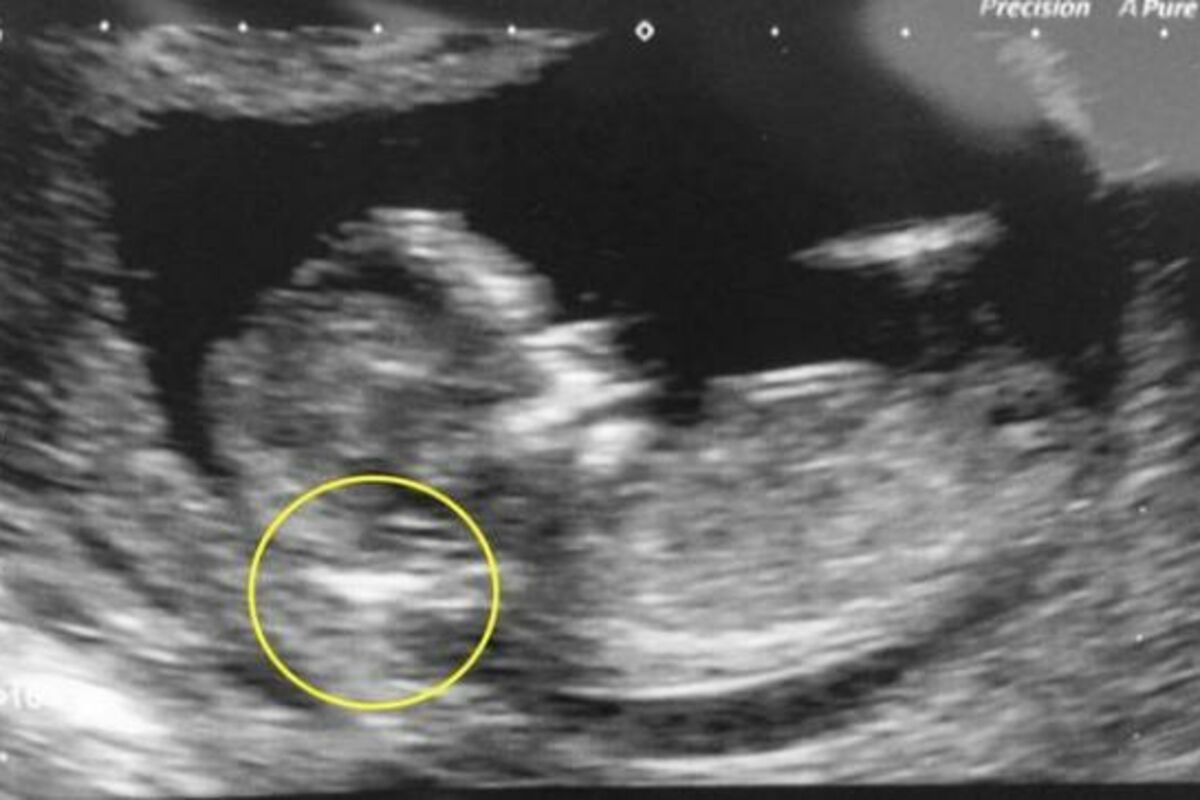

Britanka Džordan Skvajers (22) doživela je neprijatnost nakon odlaksa kod ginekologa u 12. nedelji trudnoće. Doktor joj je rekao da odmah abortira jer na ultrazvuku video veliku količinu tečnosti u potiljku bebe. Bio je prilično siguran da će dete imati Daunov sindrom.